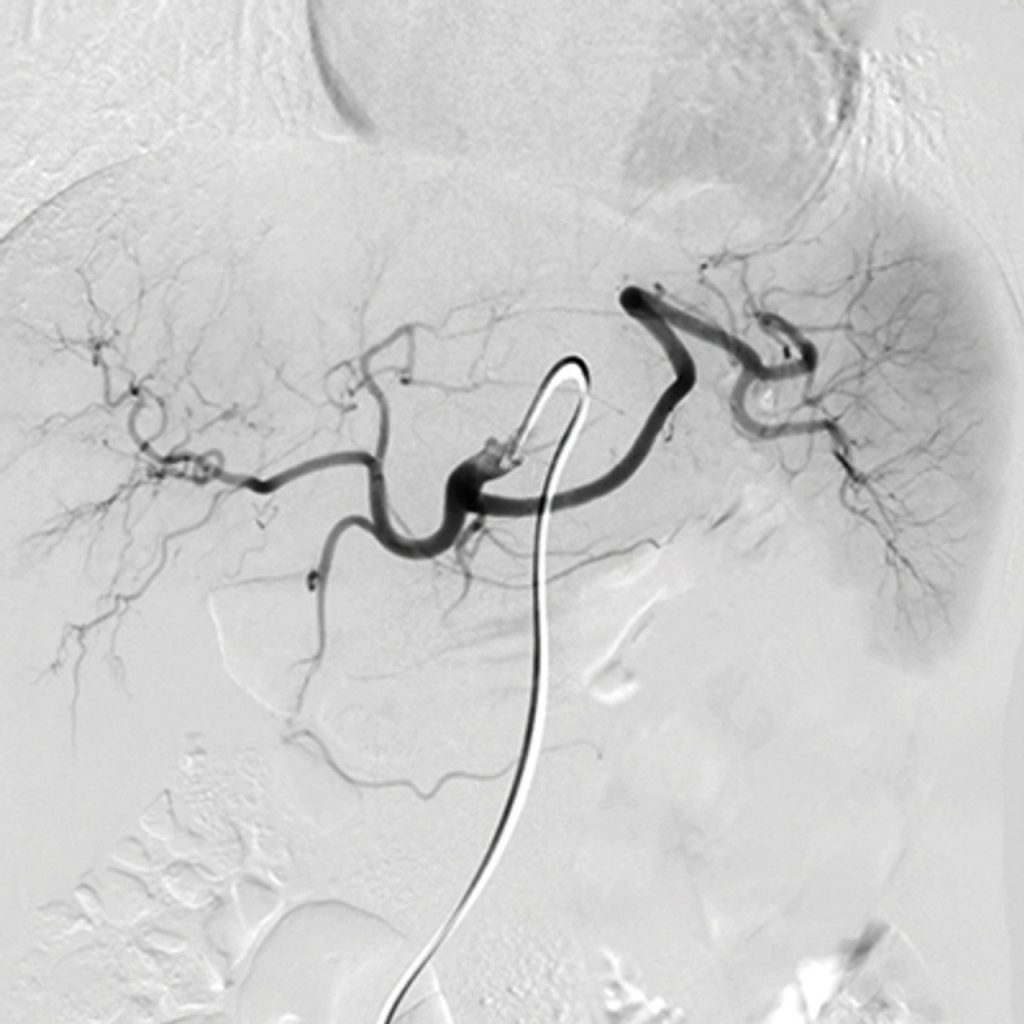

- Genicular Artery Embolization

- Uterine Artery Embolization

- Mesenteric Ischemia